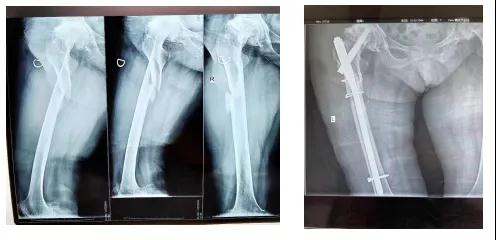

病例一:76岁女性,摔倒致右髋部疼痛活动受限,经诊断为右股骨干骨折,患者有双侧股骨头坏死病史,因手术体位摆放困难,给予PFNA系统髓内钉固定,骨折复位满意,避免长期卧床带来的并发症。

术前 术后